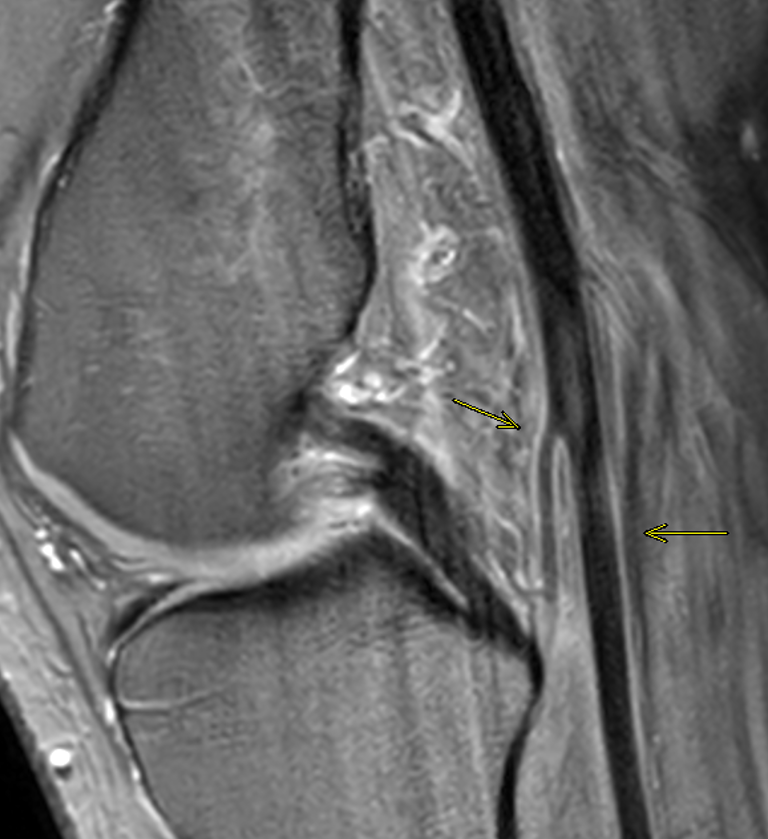

CADD gone rouge πΏ Professor Harun Gupta Siddharth Thaker (Thee/Thou/Thine) JJ Veronica Giotas (Attard) Venkatesh Mβ―οΈ PrimeRad Academy #orthotwitter

h/o trauma π€ #FOAMrad #FOAMed #radres #orthotwitter Siddharth Thaker (Thee/Thou/Thine) JJ Veronica Giotas (Attard)

What is the main differential here? π€π full link to case: pacsbin.com/c/-JxL_G9dYio JJ Siddharth Thaker (Thee/Thou/Thine) Veronica Giotas (Attard)

I will be speaking on Meniscal Ramp Lesions. Donβt miss it! Professor Harun Gupta PrimeRad Academy